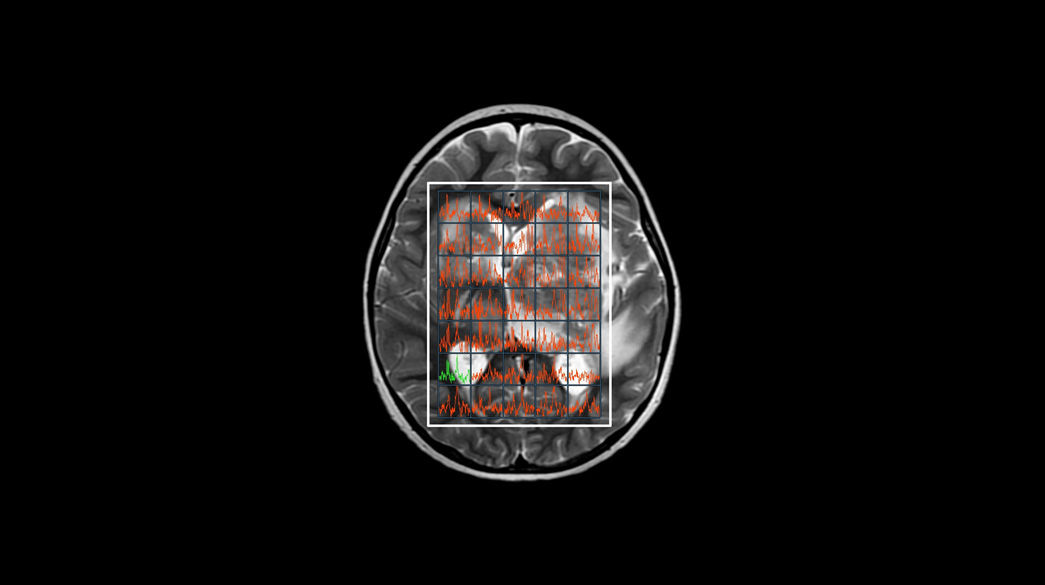

Pediatric MRI imaging applications

Precision and personalization